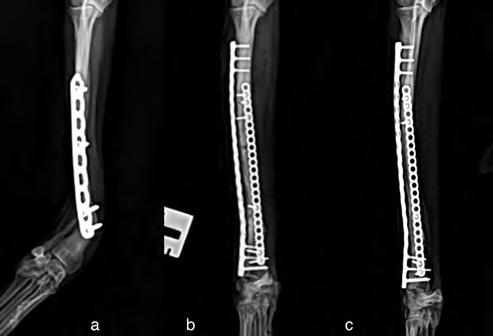

Después de la cirugía se analizaron las radiografías postoperatorias, realizándose las mismas mediciones que en la planificación, y observándose cómo los valores obtenidos tras la cirugía se correspondían con los valores planificados (Fig. 5). Se colocó un vendaje postoperatorio sencillo durante 14 días, para evitar la manipulación del área quirúrgica por parte de la pa-

Figura 5. Proyecciones radiográficas craneocaudal y mediolateral posquirúrgicas. Las radiografías muestran el resultado tras la cirugía.

Figura 7. Proyecciones radiográficas (A) craneocaudal y (B) mediolateral a los 4 meses de la cirugía. Las imágenes muestran la avanzada consolidación de la ostectomía.